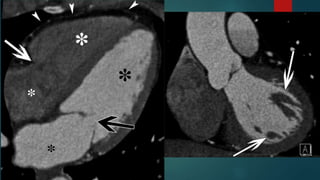

MITRAL VALVE (Leftatrioventricular valve)  Bicuspid valve  Two leaflets anterior and posterior  Leaflets are attached to chordae tendinae  Arise from two large papillary muscles (anterolateral and posteromedial)

• #39 Horizontal long-axis MPR image shows the LV (large black *), RV (large white *), LA (small black *), right atrium (RA) (small white *), MV (black arrow), tricuspid valve (white arrow), and pericardium (arrowheads). The latter structure is normally very thin. Three-chamber MPR image shows the LV papillary muscles (arrow) and chordae tendineae (arrowheads).